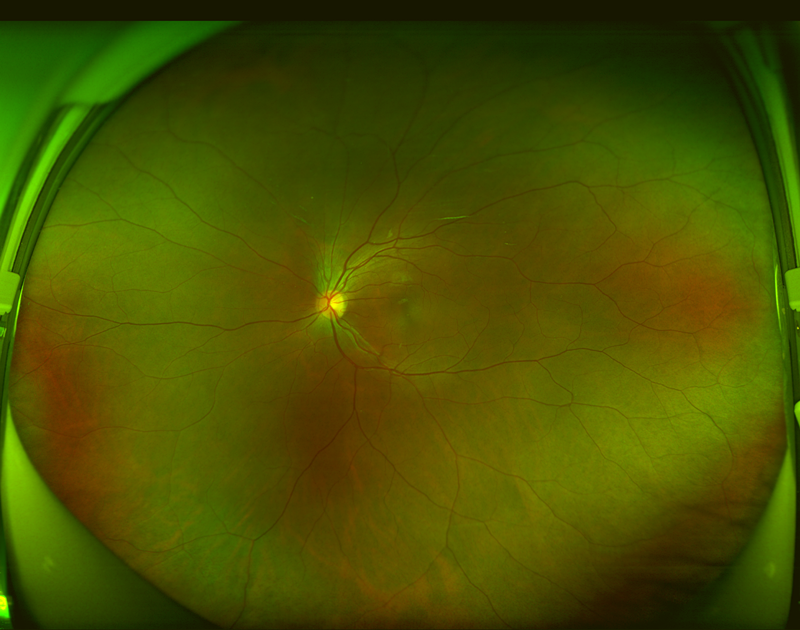

| 图一:糖尿病视网膜病变患者超广角眼底彩照; | 图二:正常眼底超广角眼底彩照 |